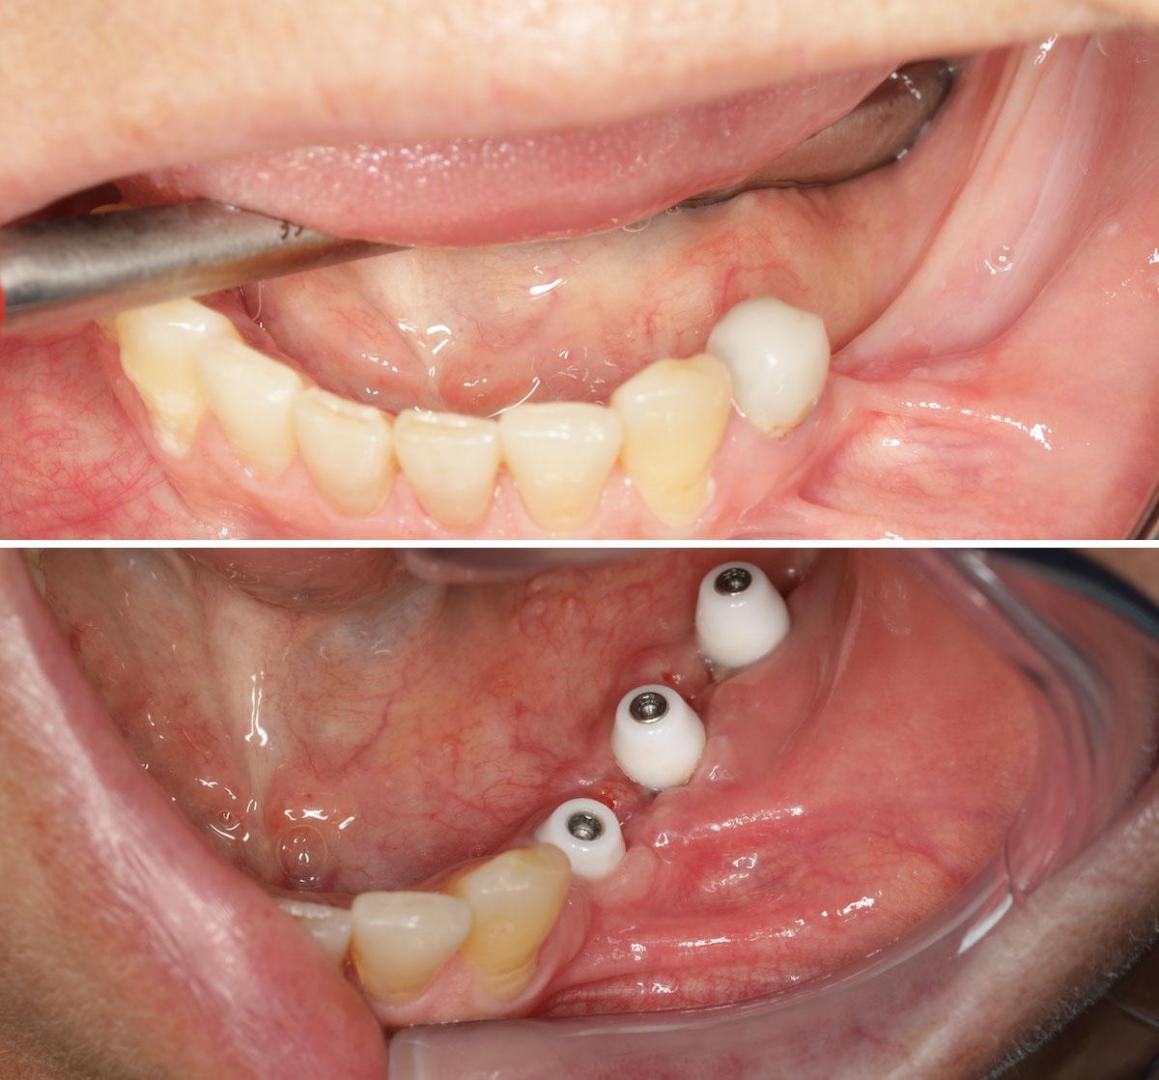

Los implantes dentales se han convertido en una de las principales y más eficaces alternativas para la sustitución de las piezas dentales perdidas. Entre otras ventajas, presentan una funcionalidad similar a la de los dientes naturales, mantienen las propiedades de la estructura ósea que los acoge y tienen el mismo aspecto que la dentadura propia.

Si el tratamiento se ha ejecutado correctamente, no es fácil distinguirlos de las piezas del paciente. Además, con un mantenimiento adecuado, pueden durar toda la vida.

En ocasiones, antes de colocar implantes dentales es necesario regenerar la masa ósea de la zona de la boca que los acoge. Tradicionalmente, esta actuación se realizaba por la falta de hueso, pero hoy día hay que considerar también otros factores, como la mejora de las propiedades mecánicas, para asegurar que los implantes tengan una larga vida útil y no causen enfermedades.

Puede afirmarse que, en los últimos años, se ha producido un cambio en el concepto de regeneración ósea para implantes dentales. Antes, se colocaba hueso principalmente por la atrofia de la zona. Como es sabido, si pasa cierto tiempo desde la pérdida del diente hasta la colocación del implante, la masa ósea pierde sus propiedades. Carece de vascularización, disminuye su densidad en altura y anchura y, por tanto, no dispone de espacio suficiente para alojar los componentes del implante.

LA REGENERACIÓN DEL HUESO REVIERTE LA TENDENCIA A LA ATROFIA

Ahora se sabe que la regeneración del hueso no solo es importante por la atrofia, sino también debido a la necesidad de mejorar las propiedades óseas. Es decir, hay pacientes que presentan una superficie suficiente para la instalación del implante, pero se trata de un hueso debilitado por la falta de dientes. Es un área cicatricial y poco vascularizada que probablemente no soportará a medio plazo las cargas mecánicas de la masticación, ya que naturalmente tiende a atrofiarse y a perder funcionalidad.

Por tanto, parece necesario abordar de forma generalizada una terapia de regeneración ósea antes de realizar el tratamiento, especialmente si los implantes se encuentran en zonas de gran compromiso mecánico, como los molares. De ese modo, su vida útil sea lo más larga posible y se evitará la aparición de enfermedades como la mucositis y la peri-implantitis.